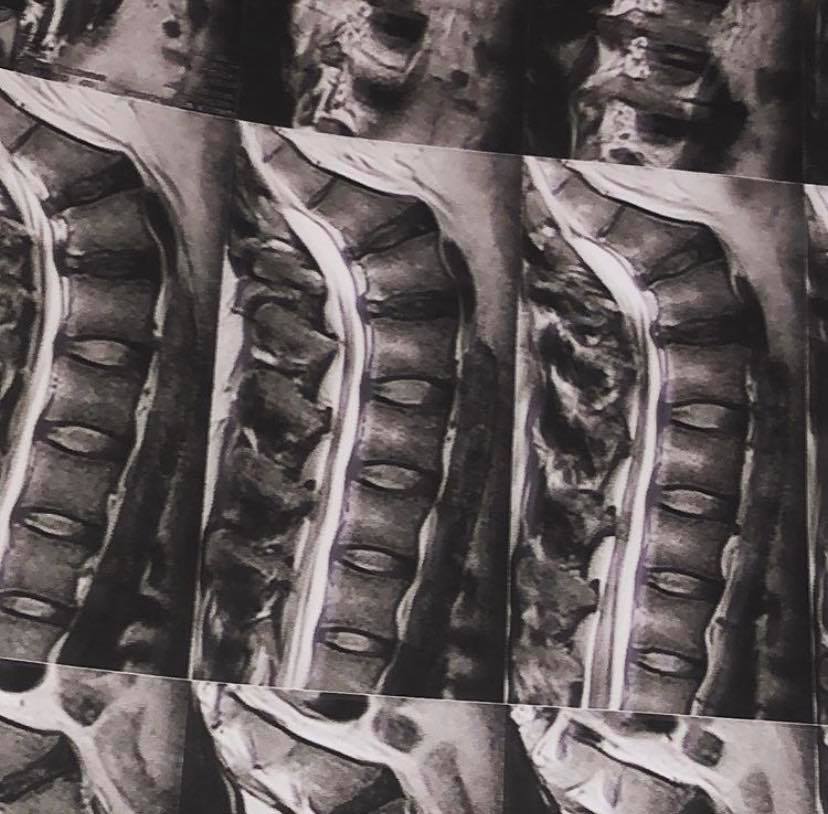

Cu toate acestea, știm cu toții că What`s Up are un stil unic de a face haz de necaz. Pe rețeaua de socializare, artistul a postat o fotografie cu o radiografie, alături de un mesaj extrem de amuzant.

„#? Să fie un tatuaj?! NU, ESTE DOAR DUBLA MEA HERNIE DE DiSC?

BiNE ai venit 2020!

p.s. Arată frumos ca tatuaj!”., a scris artistul pe contul său de socializare, în dreptul pozei. Cu toate acestea, la scurt timp, artistul a șters fotografia de pe Instagram, din dorința de a nu fi luat la rost sau la întrebări.